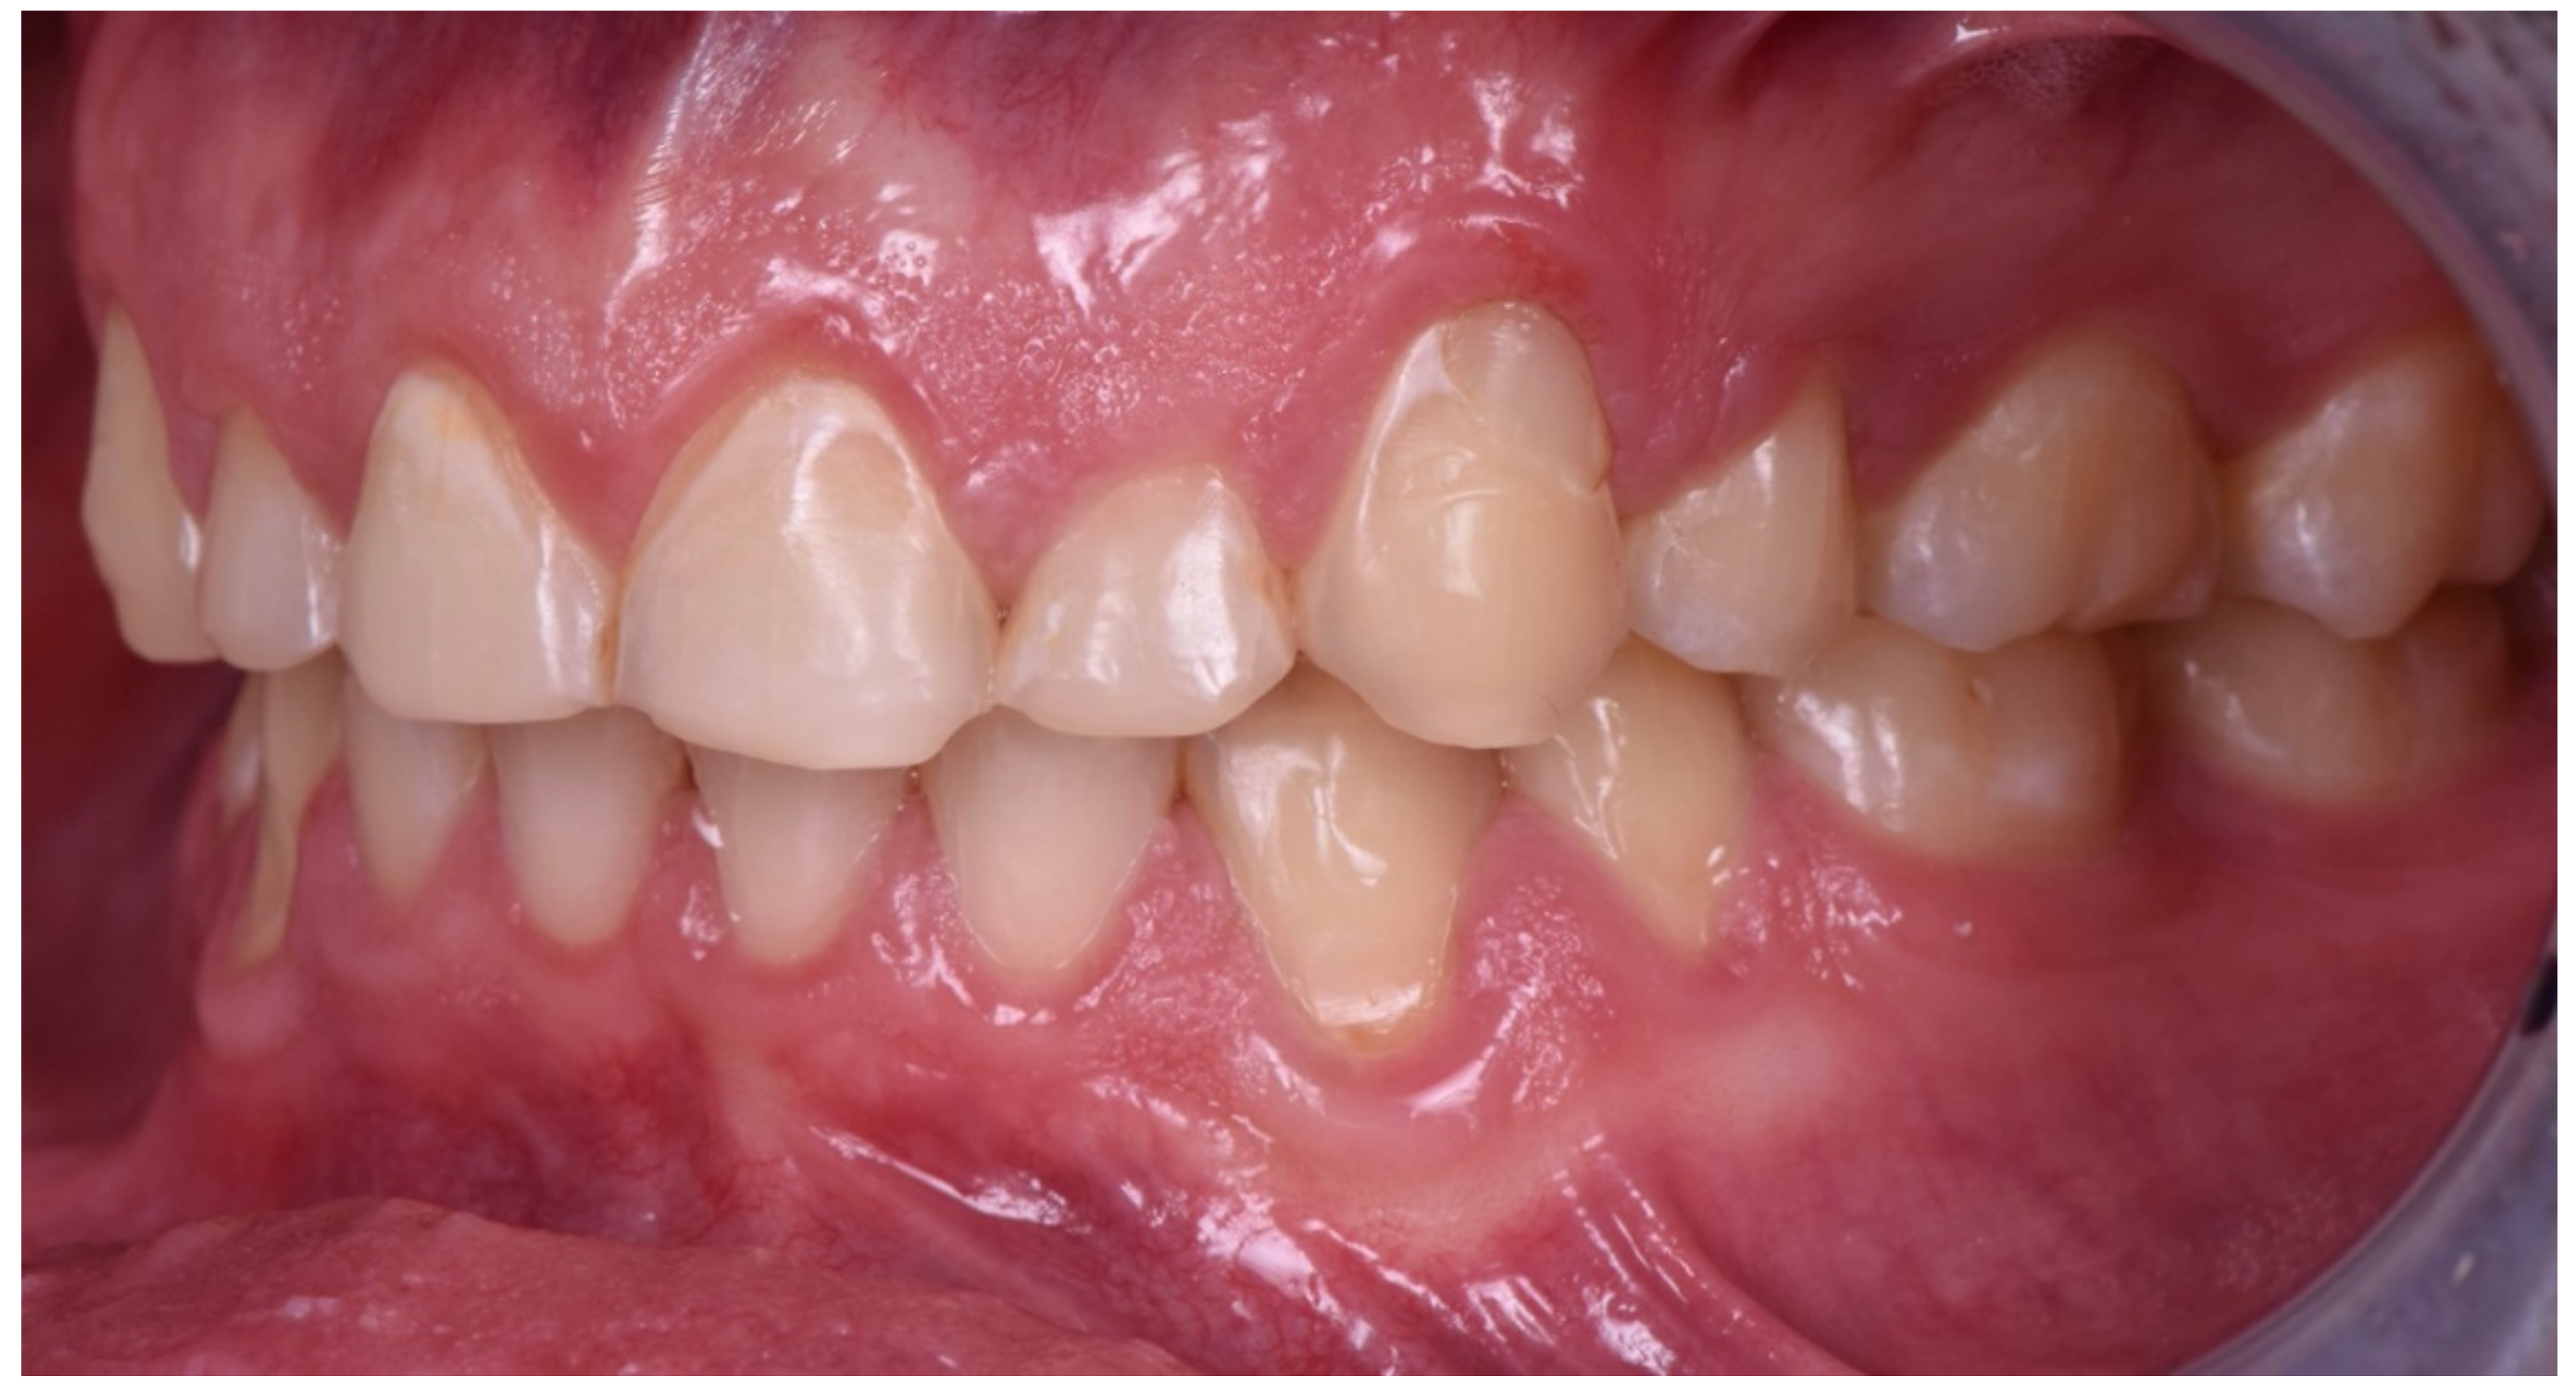

2. Clinical Report

2.1. Planning Phase

2.2. Restorative Phase